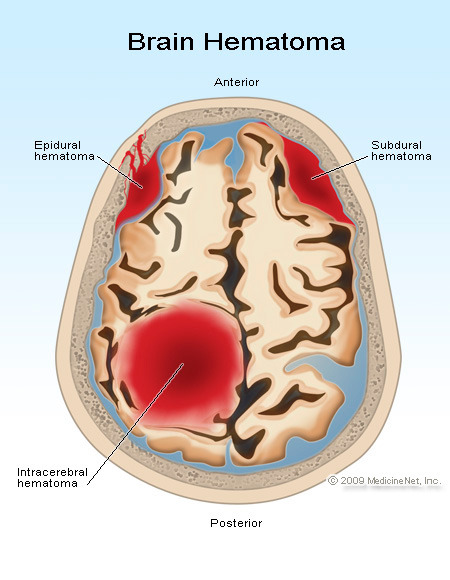

Unfortunately, many traumatic brain injuries are made worse when you do not seek medical treatment right away. Swelling of the brain or bleeding may have disabling or even fatal results hours or days after the initial trauma occurs.